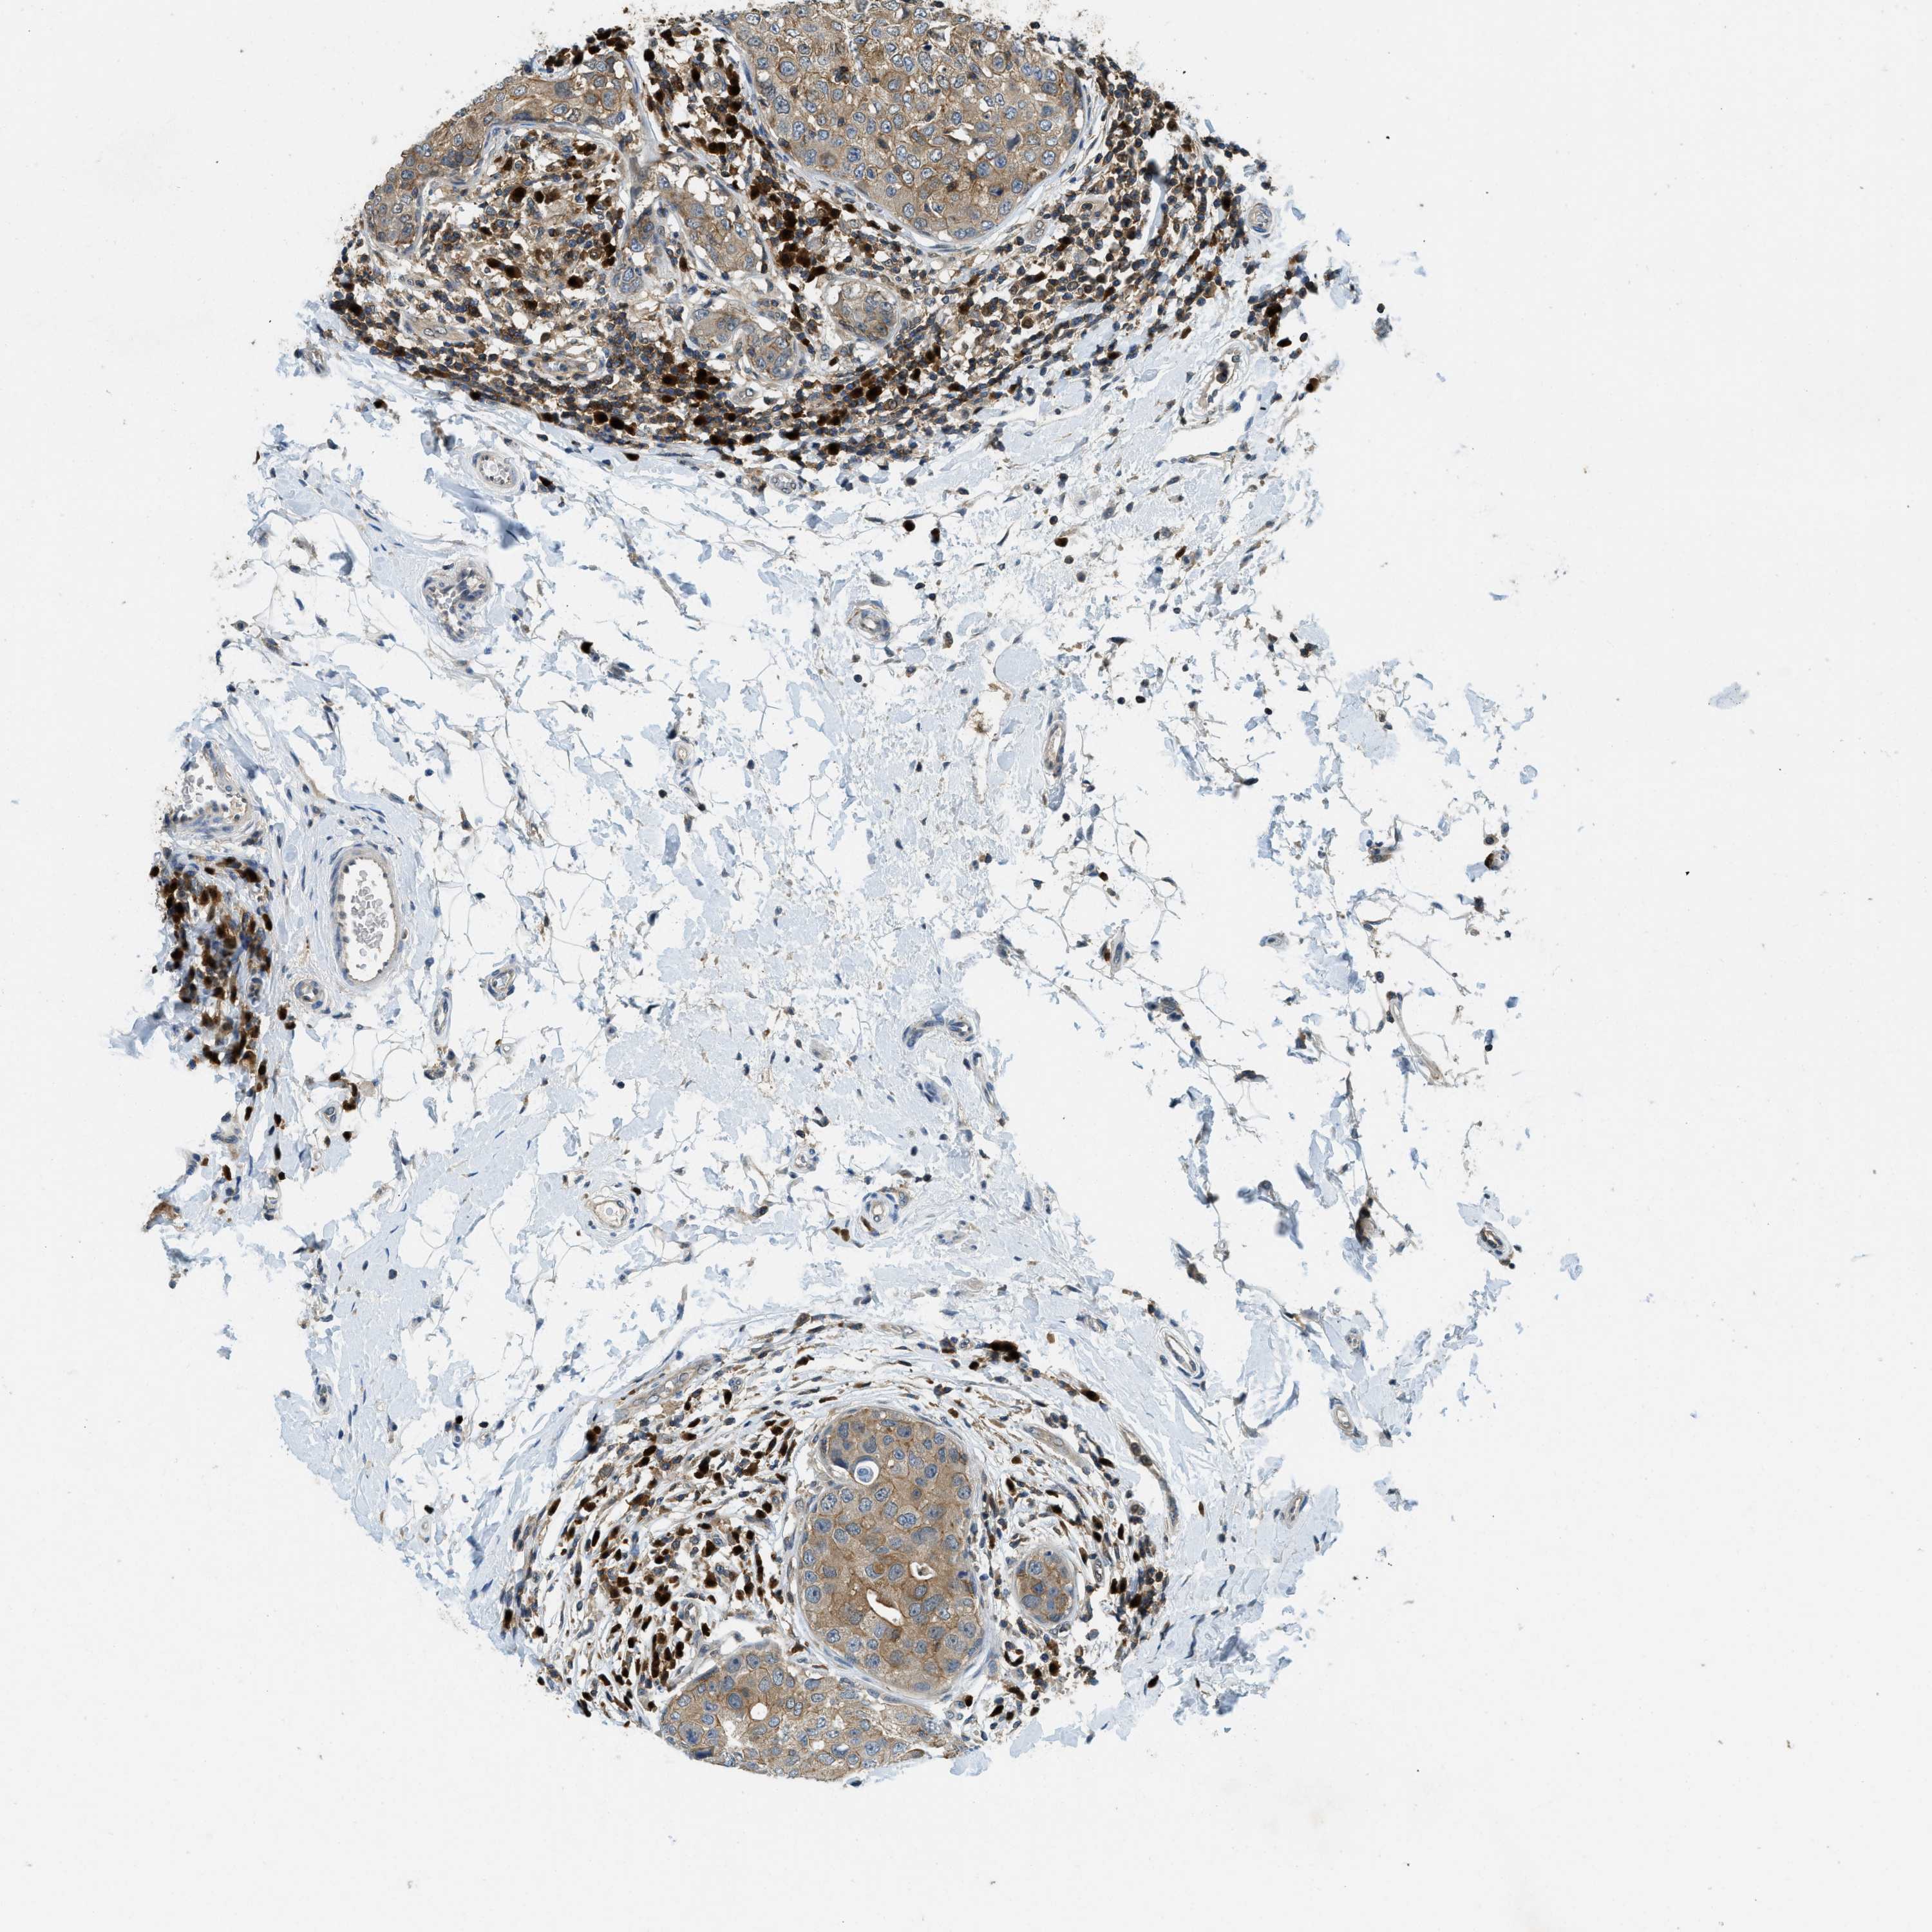

CANCER BREAST CANCER Show tissue menu

BRCA TCGA BRCA VALIDATION PROTEIN EXPRESSION

ANTIBODIES

AND

VALIDATION